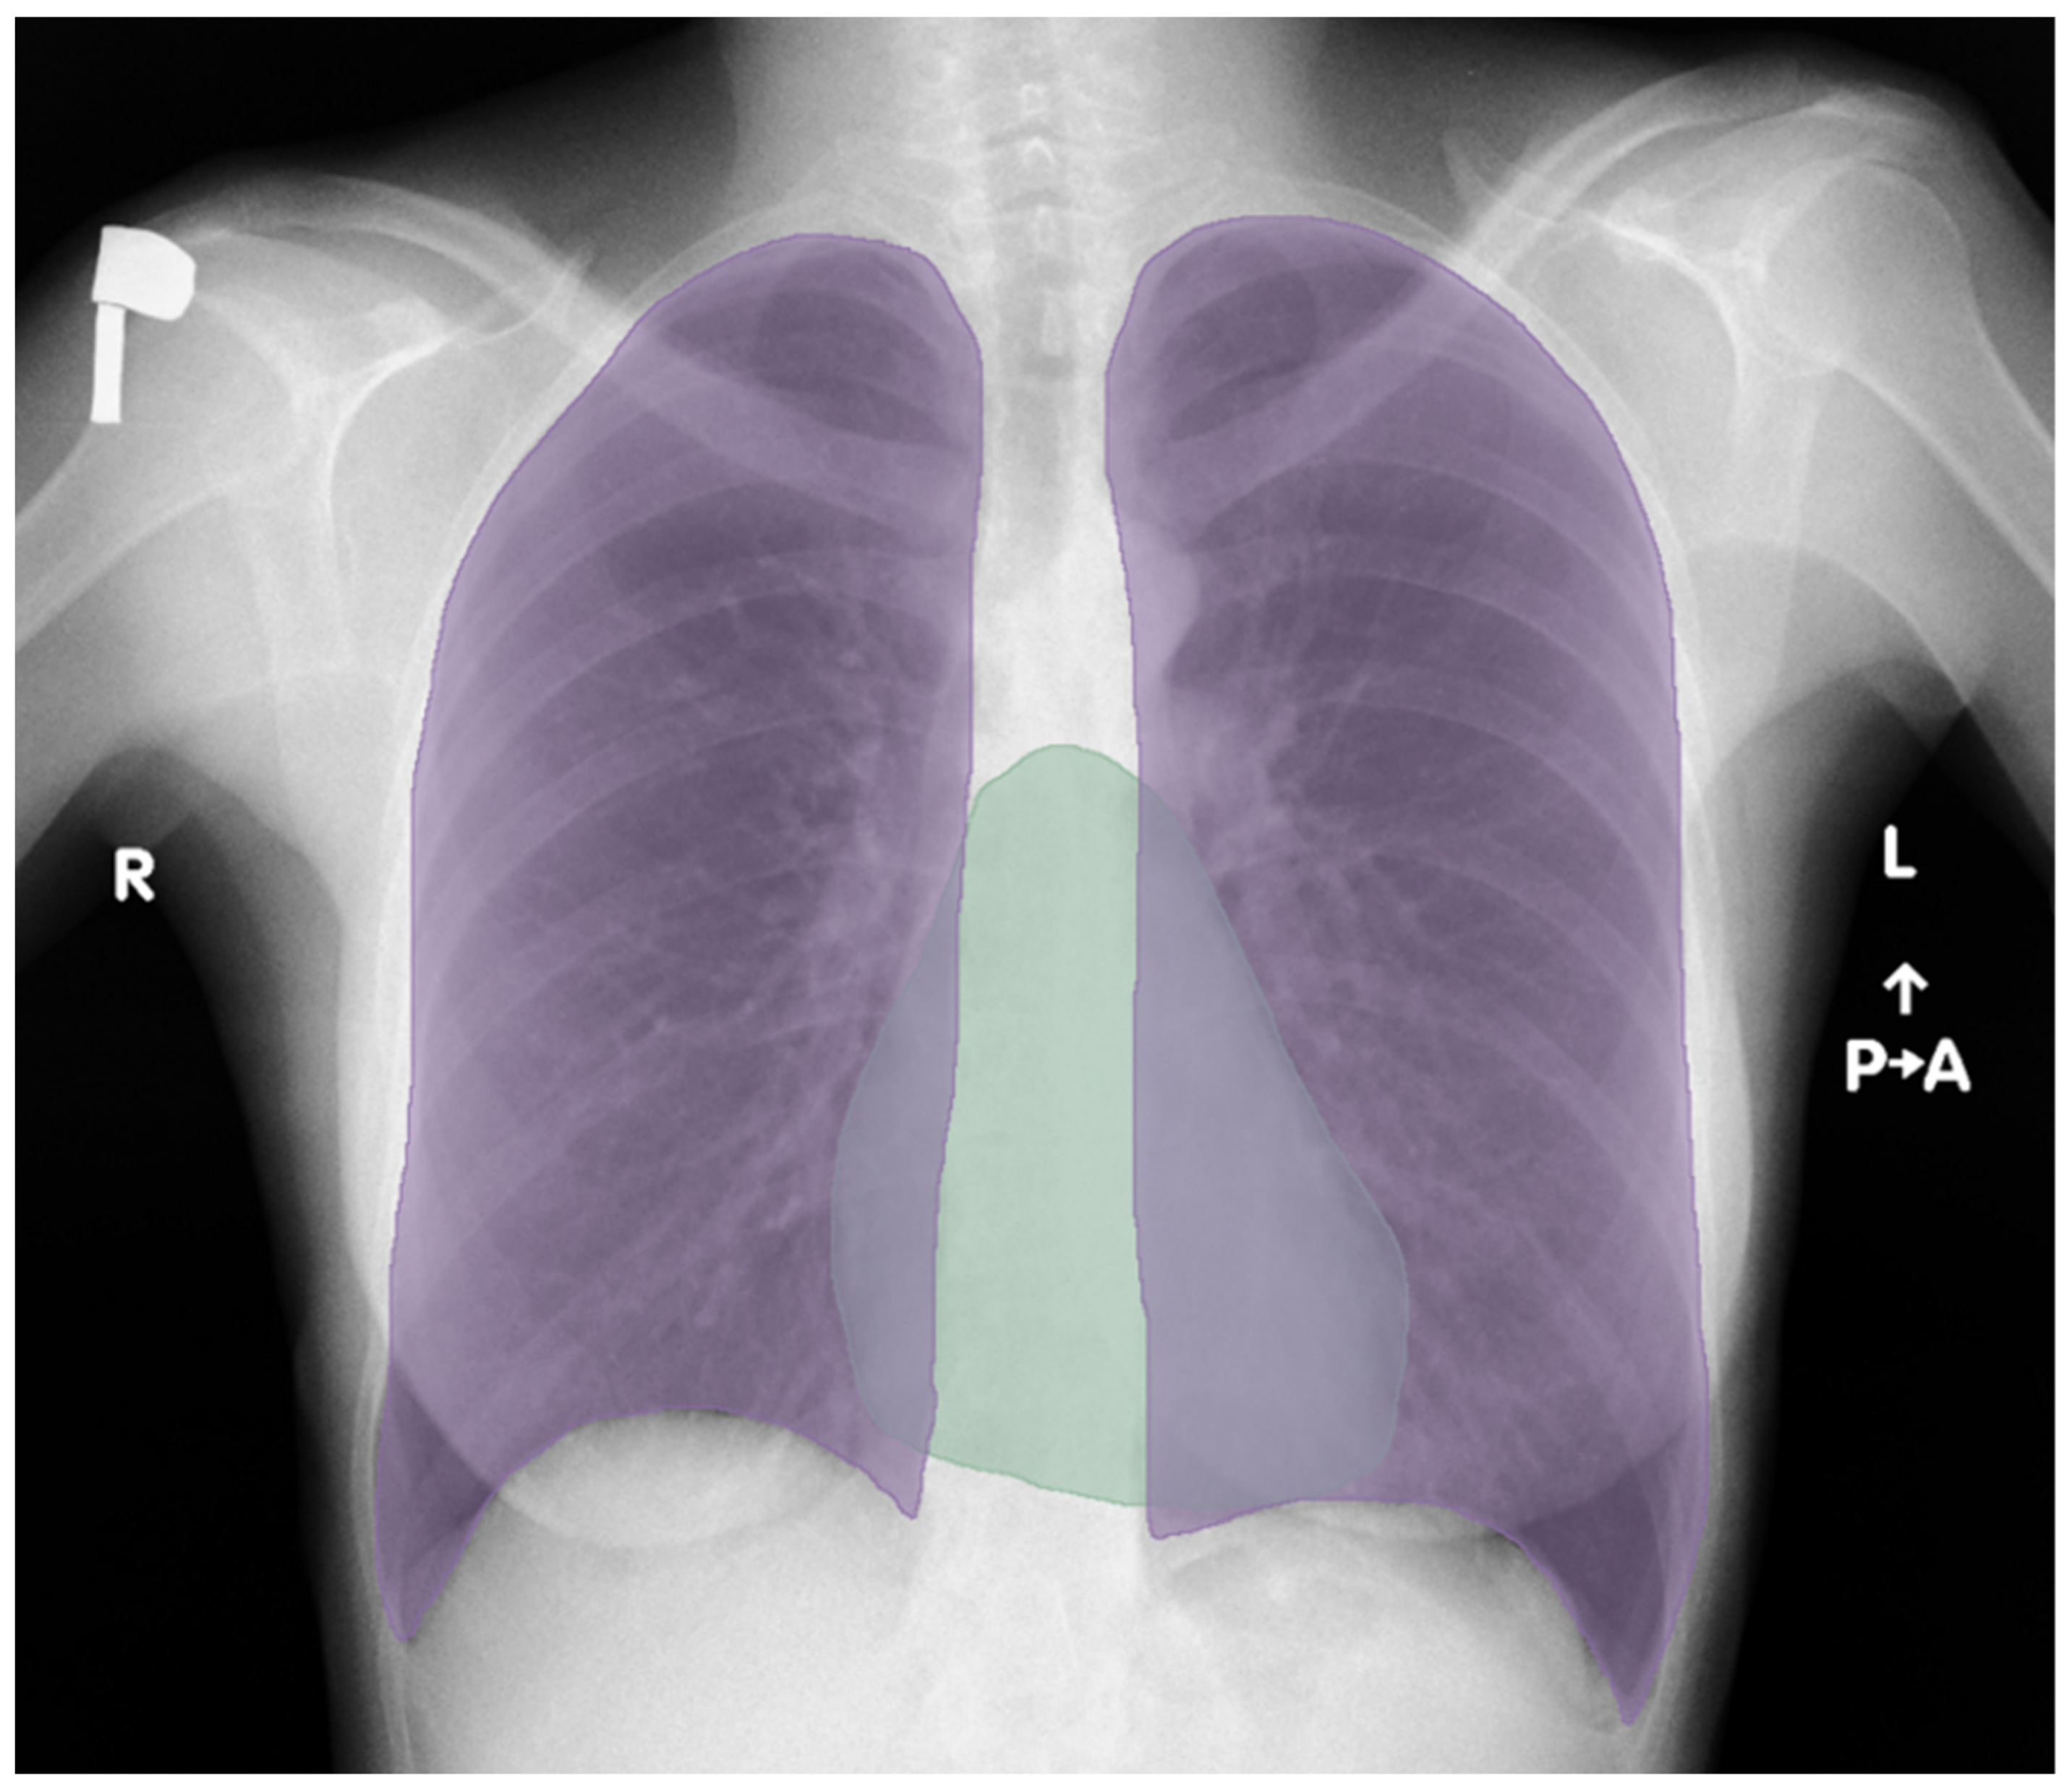

Deep Learning in Cardiothoracic Ratio Calculation and Cardiomegaly Detection

2.5. Semantic Segmentation—U-Net

2.7. Postprocessing and CTR Calculation